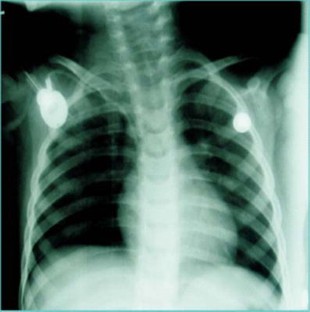

Fig. 1